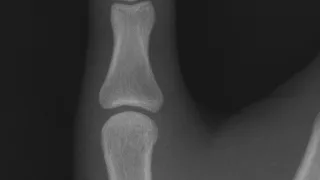

骨折歴について2 (34歳時, 右母指末節骨骨折)

整形外科スキー合宿2回目の骨折は, 右の親指の指先の骨(末節骨まっせつこつ)の骨折でした.以前の職場であった大学では, 毎年冬にスキー合宿がありました.整形外科の医師, 病棟・外来の看護師さん, 理学療法士さん, 医局秘書さんなどと一緒に,...